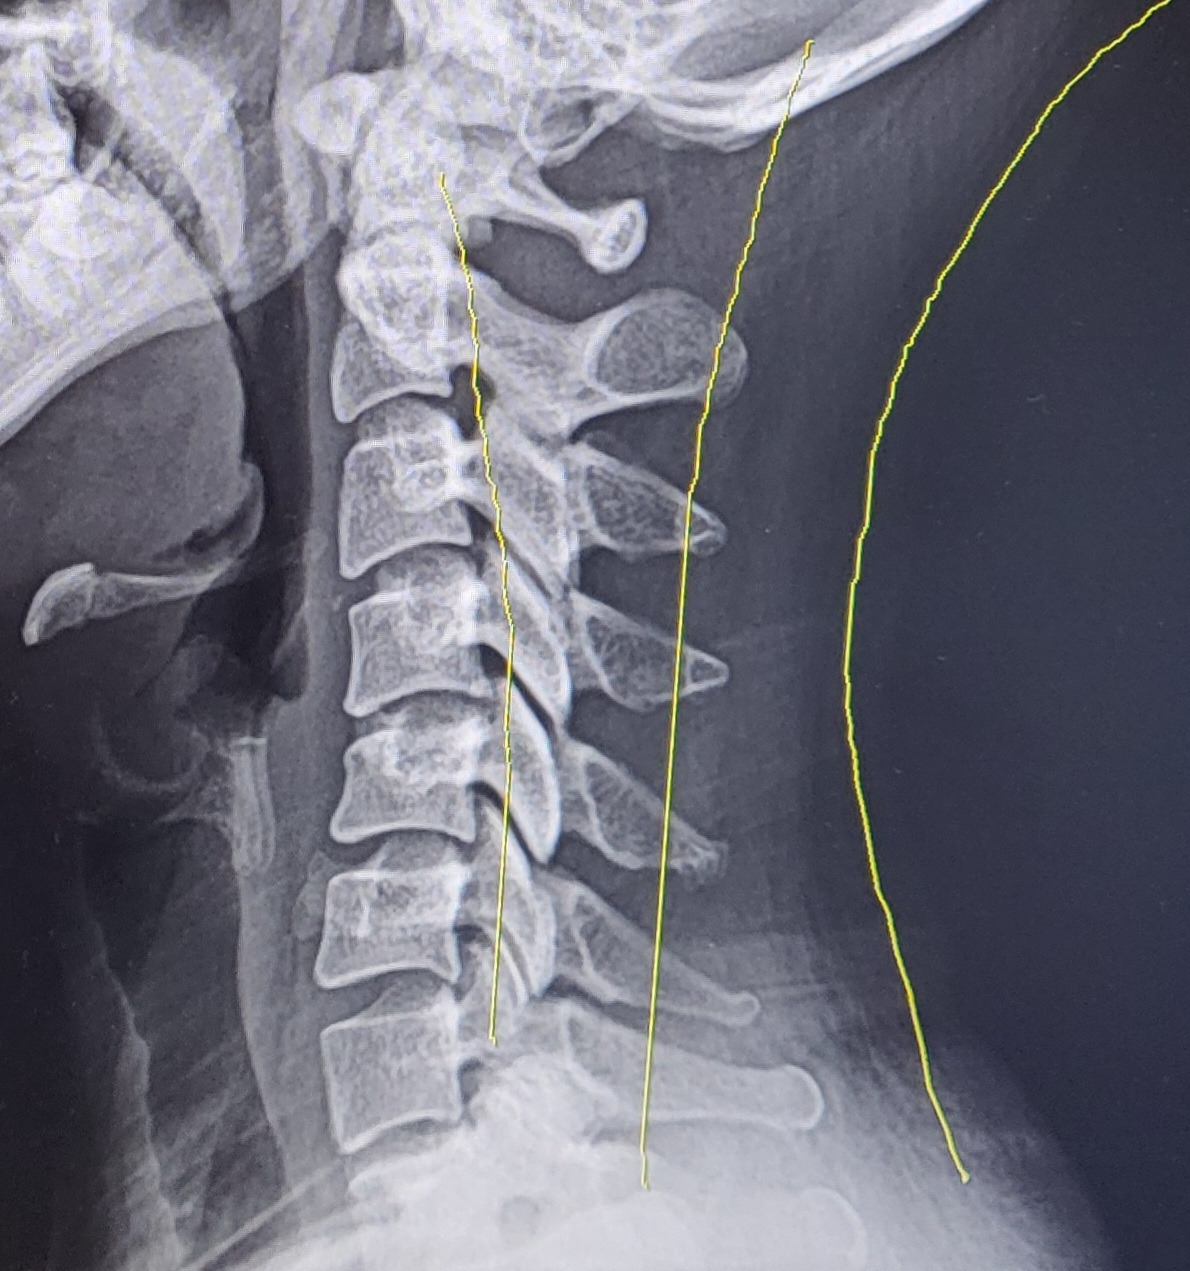

거북이를 키우고 있는 거북목 집사의 엑스레이 사진

"일자목입니다."

의사 선생님께서 사진을 보여주시며 말씀하셨다.

"네? 일자목이 뭐예요 선생님?"

"쉽게 말해서 거북목이라는 거예요. 원래 목뼈가 이렇게 C자형으로 커브를 그리게 되어있거든요? 그런데 환자분은 지금 목뼈가 일자 모양, 살짝 앞으로 휘어져있는 거북목의 형태를 보이고 있다는 말이지요. 보통 컴퓨터, 핸드폰을 많이 하시는 분들이 이런 증상이 생겨요. 특히, 누워서 핸드폰 하는 자세가 가장 안 좋습니다."